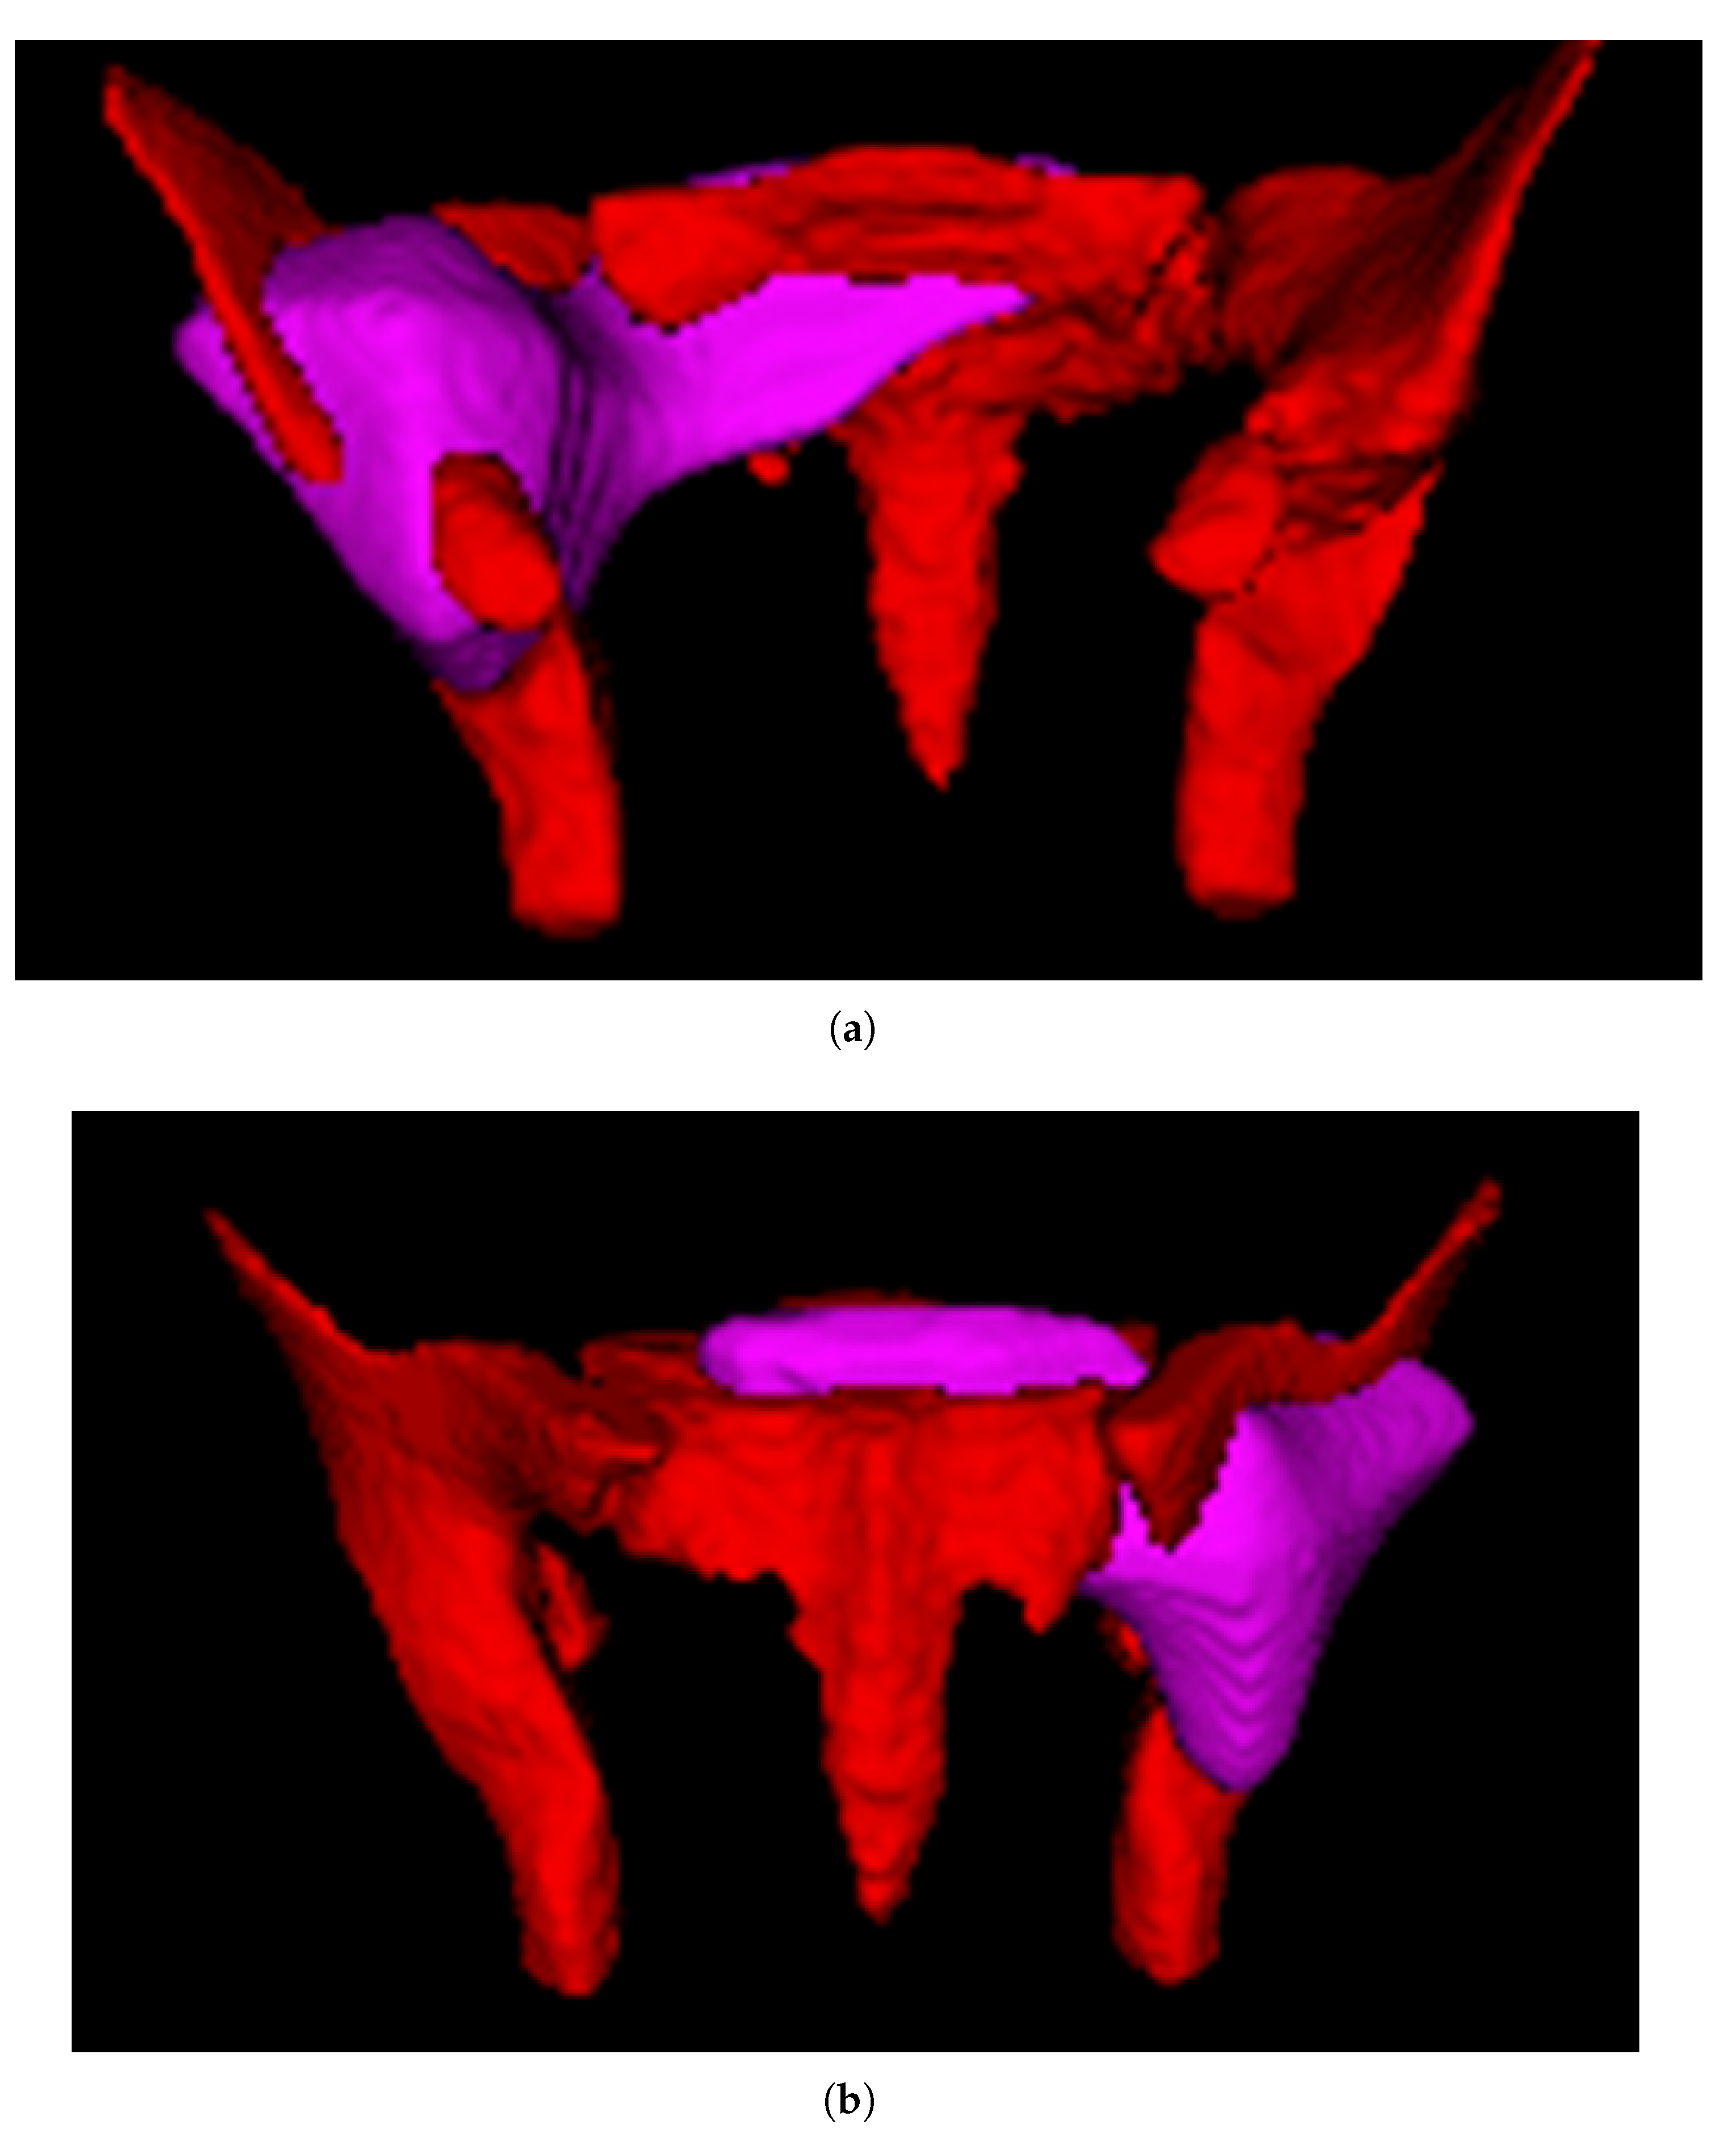

2.2. Image Preprocessing